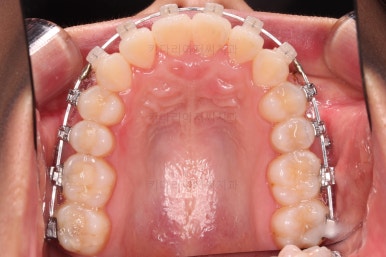

교정 시작 9개월만인데요.

벌써 치열이 가지런해졌네요.

입 안의 모습만 보면 조만간 마무리가 가능할 정도로 많은 부분들이 좋아졌는데요.

교정이라는게 단순한 교합/입 안만 보는 것이 아니라 얼굴모습과의 조화, 얼굴모습의 개선까지도 생각해야 되므로 추가적인 고려사항이 많았습니다.